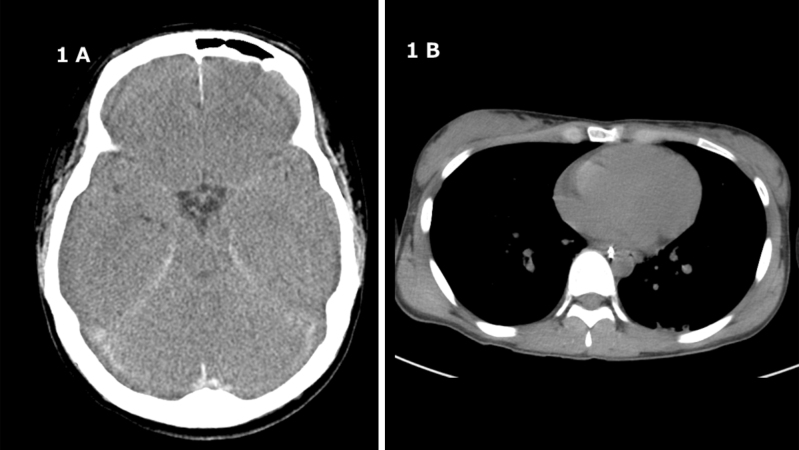

Helium inhalation has increased, but most cases are either minor injuries or deaths; there have not yet been any reported cases of brain death leading to organ donation. We report a patient who attempted helium inhalation and was declared brain dead and became an organ donor without complications. To the best of our knowledge, this is the first reported case of deceased organ donation following helium asphyxiation in Japan. The patient in cardiac arrest was found with a helium-filled vinyl bag sealed around the neck. During emergency medical transport to the hospital, a spontaneous return of circulation was obtained after 31 minutes of cardiopulmonary resuscitation. Upon hospital arrival, the physical examination revealed dilated pupils with no response to light. Electrocardiography showed widespread ST-segment depression and ST-segment elevation in augmented Vector Right, as well as elevated cardiac enzymes and decreased myocardial contractility. Head computed tomography revealed diffuse cerebral edema and loss of the gray-white matter boundary without signs of air embolism in the cerebral and coronary arteries. Despite comprehensive post-cardiac arrest care with recovery of organ function, brain death was confirmed on day 4 after hospitalization. The family consented to organ donation on the 11th day of hospitalization. The heart, lungs, liver, and two kidneys were successfully transplanted and all organs functioned. All organ grafts were functioning well at the 3-month follow-up. Our case demonstrates that brain death caused by helium inhalation is not a contraindication to organ donation.